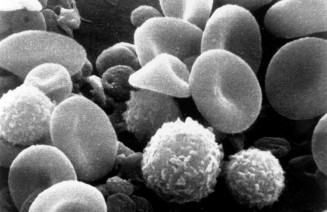

Nutrició, impuls vital

Exposició “Nutrició, Impuls Vital” al Museu Blau, el Museu de Ciències Naturals de Barcelona. Aquest projecte expositiu aprofundeix en els conceptes de nutrició i alimentació, promociona els hàbits de vida saludable i Llegeix-ne més…